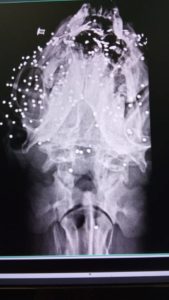

Lei è Lucia, ed è stata trovata vagante dalle volontarie nei pressi di Lenola (LT), cieca e sofferente e affetta da leishmaniosi . La sua storia potrebbe essere una delle tante storie di animali abbandonati a loro stessi dopo promesse umane non mantenute se non fosse per il referto medico che pubblichiamo e che evidenzia come il suo corpo sia pieno di piombini! Uno di questi piombini ha causato la cecità di questa buonissima cagnolina.